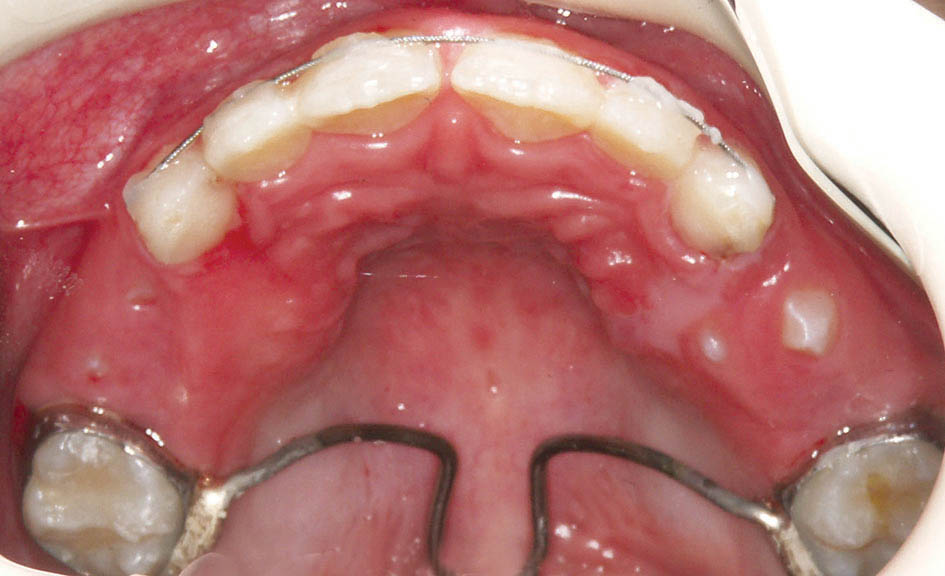

بعد از آن بایستی صبر کنیم تا تمام دندانهای دائمی رویش یابند (شکل 43-5 الی 45-5). با چنین کار سادهای شما از کلاسIII شدن، تنگی ماگزیلا، انحراف طرفی مندیبل (بخاطر کراس خلفی یک طرفه) و انحراف قدامی مندیبل (بخاطر کراس قدامی دندانها) جلوگیری میکنید. اگر قادر به اینگونه درمانها نباشید چنین بیماری دارای عوارض بسیاری میشود و در بزرگسالی نیاز به چندین عمل جراحی خواهد داشت و معمولاً نتایج درمانهای جراحی به زیبایی چنین کارهای ساده ارتودنسی (شکل 46-5) نمیشوند.

برای نگهدارنده بعد از RPE یا پالاتال بار یا پلاک Hawley میدهیم و برای نگهدانده درمان کراس قدامی اگر دیپ بایت باشد چیزی نمیدهیم و اگر دیپ بایت نباشد یک سیم twisted به بیمار میدهیم. در این بیمار یک پالاتال بار و یک سیم twisted قرار دادیم.

در این بیمار رشد پریماگزیلا و پروترود شدن انسیزورهای بالا باعث شد که لب بالا برجستهتر بشود و قرمزی آن بیشتر معلوم گردد.

چانه بیمار هم (بخاطر درمان کراس قدامی) خلفیتر قرار میگیرد و نمای کلاسIII صورت بهتر میشود.

شکل 45-5: میدلاین صحیح بیمار فوق پس از درمان